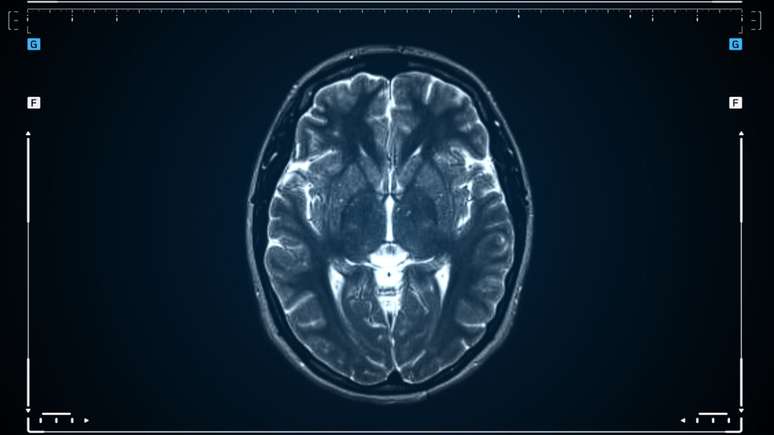

Com apoio de imagens de ressonância magnética e aprendizado de máquina, cientistas descobriram diferentes “biótipos” de depressão; entenda

Foto: Reprodução: Canva/AlpakaVideo / Bons Fluidos

Pesquisadores da Stanford Medicine estão desenvolvendo um método inovador capaz de identificar diferentes "biótipos" da depressão com o auxílio de exames de imagem cerebral. A ideia é simples e revolucionária: mapear o funcionamento do cérebro para entender quais circuitos estão em desequilíbrio. Dessa forma, é possível personalizar o tratamento de cada paciente.

Usando ressonância magnética funcional (fMRI) e técnicas de aprendizado de máquina, a equipe de Stanford analisou centenas de cérebros e encontrou seis subtipos diferentes de depressão, cada um ligado a um circuito cerebral específico. Entre eles estão os circuitos responsáveis pela atenção, emoção, prazer e controle cognitivo - áreas que, quando alteradas, geram sintomas distintos como apatia, tristeza intensa, ansiedade ou dificuldade de concentração.